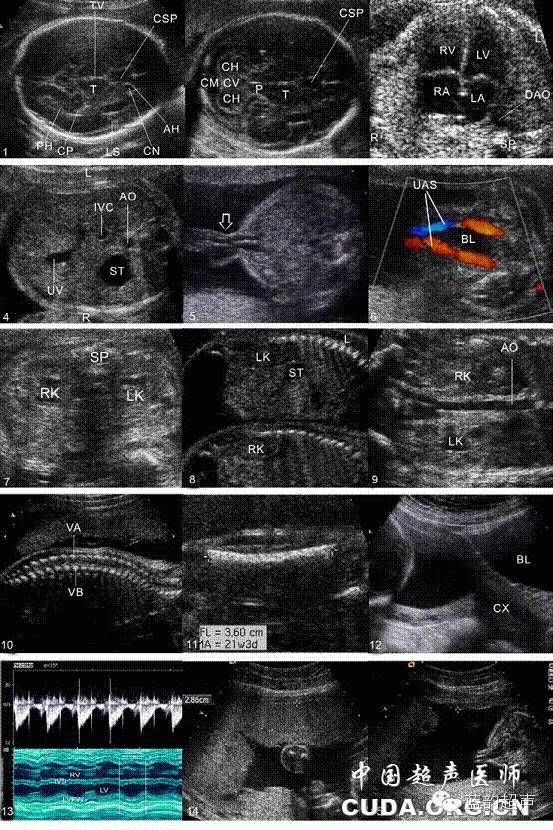

Ⅰ级产科超声检查建议存留的超声图与模式

1、丘脑水平横切面超声图及模式图,2、上腹部横切面超声图及模式图,3、股骨长轴切面超声图及模式图,4、测量胎心率图(多普勒或M型)超声图及模式图,5、测量胎盘厚度超声图及模式图,6、最大羊水池切面超声图及模式图T:丘脑;CSP:透明隔腔;TV:第三脑室;PH:侧脑室后角;CP:脉络丛;LS:大脑外侧裂;CN:尾状核;AH:侧脑室前角;R:右侧;L:左侧;ST:胃泡,UV:脐静脉,IVC:下腔静脉;AO:腹主动脉;FL:股骨